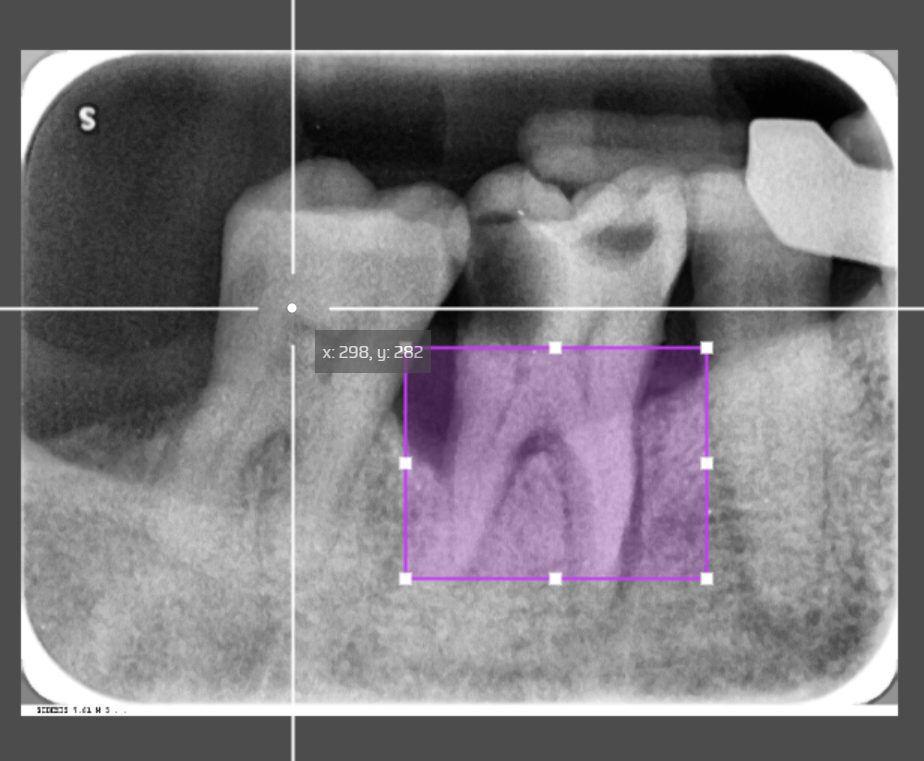

The Effect of the Region of Interest (ROI)

The solution to this was a hybrid classification. Instead of relying 100% on the full image, we introduce a second input data, a cropped highlighted image which simulates the dentist’s analysis area, into the same neural networks. This specific area is the Region of Interest. Then, we apply a scale layer for both inputs with weight fusion. The AI model now relies on

The full image (50%): First input representing the model learn without human intervention, providing the overall context of the patient’s dental cavities.

The cropped ROI (50%): Second input representing the model learn the area created specifically where dentists look within ROI coordinates.

The combined weights: A combination of the full image input and the cropped ROI input for a single prediction.

Image created with www.makesense.ai